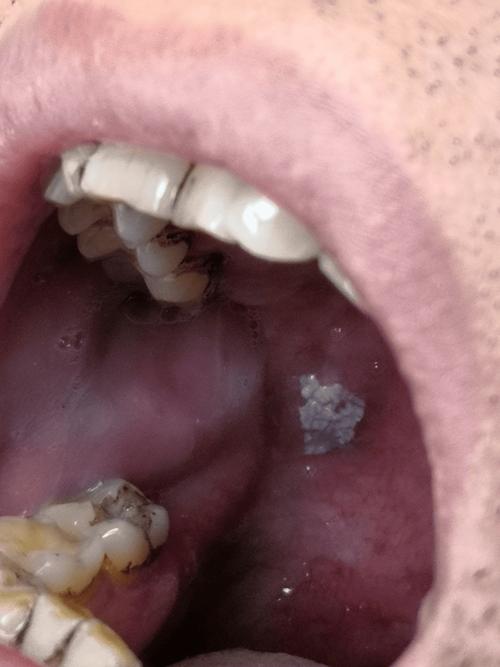

口腔白斑

这是一种癌前病变,虽然大部分白斑终身不会癌变,但有癌变的风险,它指的是口腔黏膜上出现的、不能用任何物理方法(如擦除)去除的白色或灰白色的斑块。

- 特点:

- 表面粗糙、质地较硬,有时有裂纹或溃疡。

- 边界清晰,形状不规则。

- 关键点:虽然初期可能无痛无痒,但需要定期复查,因为存在一定的癌变率。特别是长期吸烟、饮酒、嚼槟榔者,是高危人群。